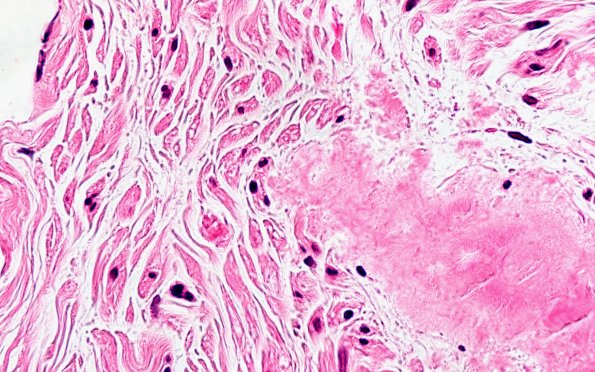

1A3 Amyloid (Case 1) H&E 100X 5

The first is characterized by large amorphous amyloid deposits, many in a perivascular distribution. (H&E)